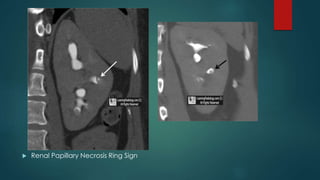

Renal papillary necrosis (RPN)

 Renal Papillary Necrosis Ring Sign